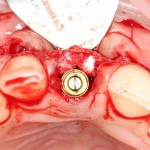

Благодаря своим свойствам. Bio-Oss Collagen не забивается в подготовленную лунку импланта, не съезжает и не сползает при его установке:

Вот, собственно, и всё. Далее, наш биоматериал ведет себя совершенно также, как и обычный Bio-Oss — он быстро пропитывается кровью и отлично удерживается на месте:

В данном случае мы планировали закончить этап немедленной установкой временной коронки, этим займется ортопед через полчаса после установки импланта. Пока же, я закрываю имплантат формирователем десны и накладываю швы: